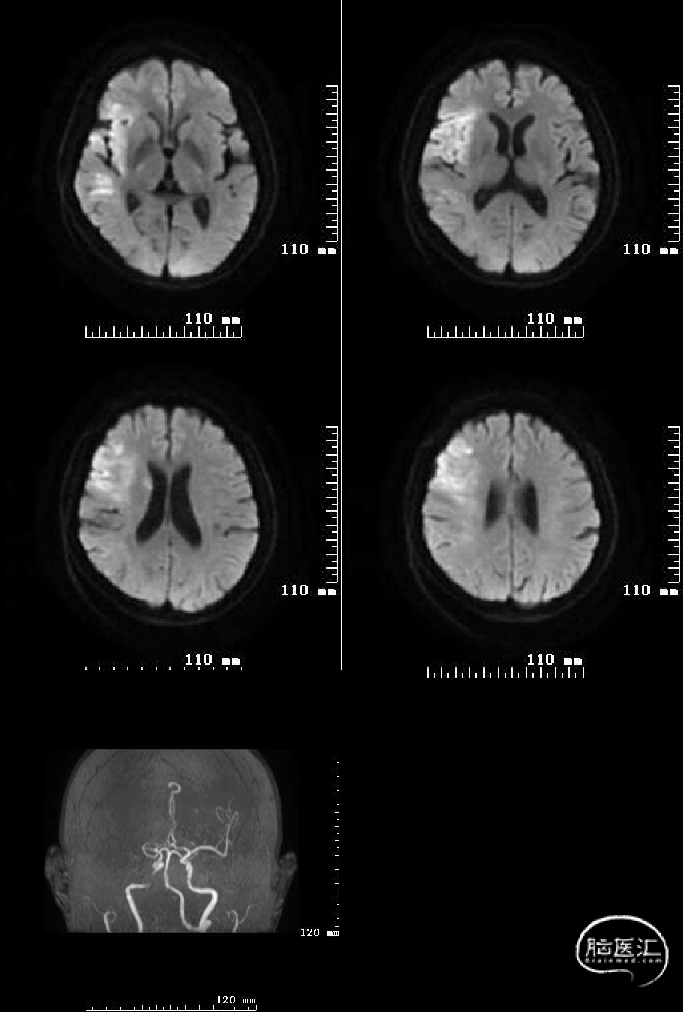

头颅MRI+DWI+MRA:右侧额颞叶及侧脑室旁急性脑梗塞,右侧大脑中动脉闭塞?右侧颈内动脉破裂孔段狭窄?

脑血管造影证实:右侧大脑中动脉M1段闭塞。

采用SWIM技术取栓,一把通,远端血流TICI分级3级。

专家点评

该例为中年卒中,低NIHSS分值大血管闭塞,有明确静脉溶栓禁忌的轻型致残性缺血性卒中,结合房颤病史,考虑心源性脑栓塞无疑。对于时间窗内低分值大动脉闭塞AIS的血管内治疗,目前还没有强有力的RCT研究证据,针对该例患者有明确大动脉闭塞,从DWI看其实患者脑梗死核心并不小,只是恰恰梗死到非功能脑区或我们不常用的功能区而已,这也反应了NIHSS存在一定局限性。时间就是大脑,临床遇到此类病例应当机立断,在条件请允许的情况下及时开通脑动脉恢复脑血流灌注才是王道!同时,该例患者及时清除右侧大脑中动脉阻塞的血栓,也算是消除了病情加重恶化的隐患,试想一下,如果当初我们选择保守治疗,随着时间推移,阻塞在右大脑中动脉M1段的栓子有可能自溶崩解,崩解的栓子再栓塞到功能区供血动脉而错失取栓良机,那可能后果是难以接受的。